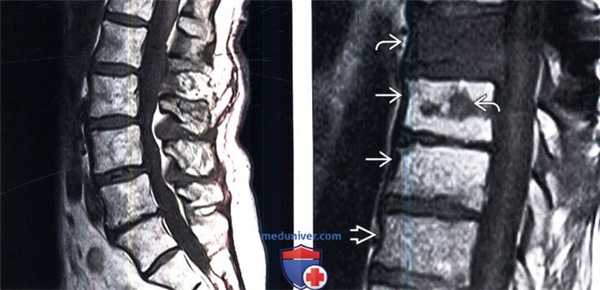

Среди экстрадуральных опухолей на первом месте стоит метастатическое поражение. Стандартный протокол МРТ исследования позвоночника при подозрении на метастатическое поражение состоит из Т1-зависимых сагиттальных МРТ и Т2-зависимых МРТ с подавлением сигнала от жира. Литические метастазы замещая костный мозг выглядят гипоинтенсивными на Т1-зависимых МРТ позвоночника. На Т2-зависимых МРТ позвоночника они могут быть гипоинтенсивными, изоинтенсивными, если они склеротические, либо яркими, если они литические, особенно при подавлении сигнала от жира. Метастаз может диффузно поражать костный мозг позвонка или быть очаговым. На самой ранней стадии диффузного поражения при МРТ позвоночника заметно исчезновение сигнала от вертебробазилярной вены, процесс захватывает ножки дуг и задние структуры позвонка. Распространение на мягкие ткани вдоль позвоночника лучше видно на Т1-зависимых корональных МРТ, а сдавление спинного мозга на сагиттальных МРТ позвоночника. На последнем этапе желательны контрастированные Т1-зависимые МРТ в сагиттальной и поперечной плоскостях. Чуствительность МРТ позвоночника превышает 90%, что заметно превосходит радионуклидную диагностику. В плане отличия метастазов и доброкачественных заболеваний МРТ позвоночника не абсолютно надежна. Дифференциальная диагностика с гематологической патологией – плазмоцитомой, лимфомой и лейкозами практически невозможна и требует аспирационной биопсии. Реакцией костного мозга на МРТ позвоночника, напоминающей метастатическое поражение, сопровождаются доброкачественные переломы. Однако МРТ сигнал выраженно неоднородный, задние структуры и костный мозг в заднем отделе тела позвонка остаются интактными. Более надёжным в плане дифференциальной диагностики является использование диффузионное-взвешенных МРТ позвоночника. При доброкачественном переломе через 1 – 3 месяца сигнал возвращается к норме.